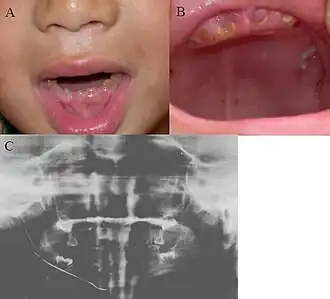

![]() Imagen clínica de la dentinogénesis Imperfecta y Ortopantomografía]] | ||

Desde el punto de vista clínico, los tres tipos comparten diversas características, en ambas denticiones, se muestra un aspecto opalescente, con una translucidez rara y de color que varía del café amarillo al gris azulado. Toda la corona manifiesta cambio de coloración debido a la dentina anormal subyacente. A pesar de que el esmalte es normal tanto en su estructura como en su composición química se fractura con facilidad, al parecer se debe al soporte deficiente que proporciona la dentina anormal.

Características Radiográficas

Radiográficamente la D.I. se caracteriza por la presencia de dientes con coronas bulbosas, con una constricción en el cuello y raíces cortas y delgadas. Se observa obliteración precoz, parcial o total de las cámaras pulpares por la formación continua de dentina. Estas características se presentan tanto en la dentición temporal como permanente. Frecuentemente se observan fracturas radiculares múltiples, en particular en personas de edad. El cemento, la membrana periodontal y el hueso alveolar aparecen normales. Estas características son comunes para la D.I. tipo I y II mientras que en la tipo III la dentina aparece delgada, las cámaras pulpares y conductos radiculares son muy grandes y dan la apariencia de conchas delgadas de dentina, razón por lo que se llama a esta entidad "dientes en concha". Adicionalmente se presentan exposiciones pulpares múltiples y radiolucencias periapicales.